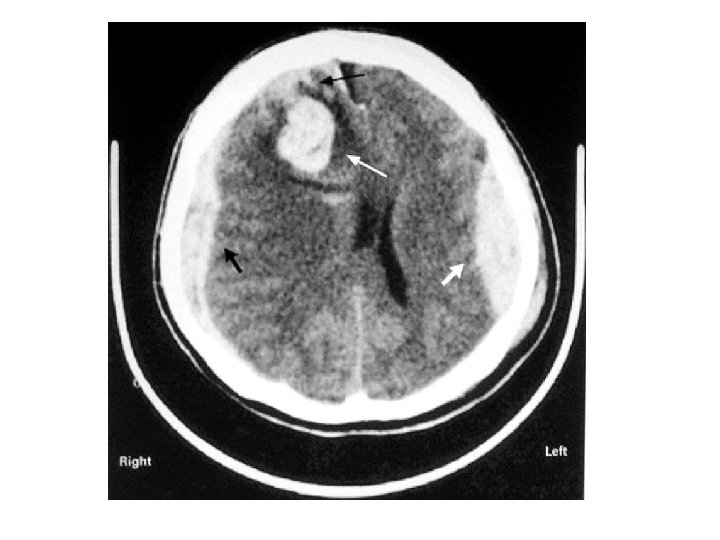

Les différentes lésions 2/2 • Hématome extra-dural – L'hématome extra-dural ou épidural est une accumulation de sang entre l'os du crâne et la dure-mère (enveloppe fibreuse du cerveau faisant partie des méninges). L'hématome extra-dural est une urgence chirurgicale absolue. Il se développe en quelques heures et peut entraîner la mort du patient par engagement cérébral si rien n'est fait. • Hématome sous-dural – Il s'agit d'un épanchement sanguin situé entre, en dehors la dure-mère, et en dedans l’arachnoïde. Il peut survenir de façon aiguë, au cours des heures suivant le traumatisme (hématome sous-dural aigu). Il est alors fréquemment associé à une contusion cérébrale dont peut dépendre le pronostic. Il peut aussi se constituer à bas bruit, et se démasquer quinze jours, voire des semaines après un traumatisme relativement peu important (hématome sous-dural chronique). • Hémorragie intracérébrale – Il s'agit d'un saignement à l'intérieur du parenchyme cérébral. • Hémorragie méningée – Une hémorragie méningée est observée dans 1/3 des traumatismes crâniens sévères. Elle peut être secondaire à la lésion d'un vaisseau méningé, ou bien à une suffusion hémorragique à partir d’un foyer de contusion du cortex cérébral.